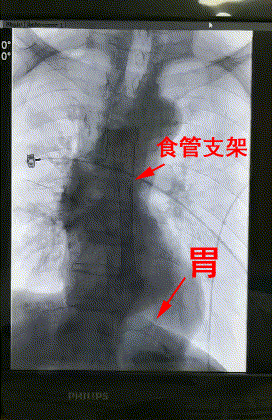

爲了解除患者的病痛,内三科主任李旭丹組織專家讨論,一緻認爲采用DSA下食管支架置入術是理想的方案。手術能同時解決2個問題:一是擴張狹窄的食管,讓患者可以進食;二是封閉食管與氣管之間的瘘口,使食物不會進入肺裏引起肺部感染。

3月28日上午,楊阿姨被送進了介入手術室,李旭丹主任等專家根據術前方案上台施術,先采用飛利浦DSA開展食道造影,明确食道狹窄端及瘘口位置,後經導絲引入食管支架釋放于準确位置。DSA顯示支架成功擴張食管狹窄端并封閉瘘口,順利完成手術。

△術後DSA造影顯示:支架成功擴張食管狹窄端并封閉瘘口。